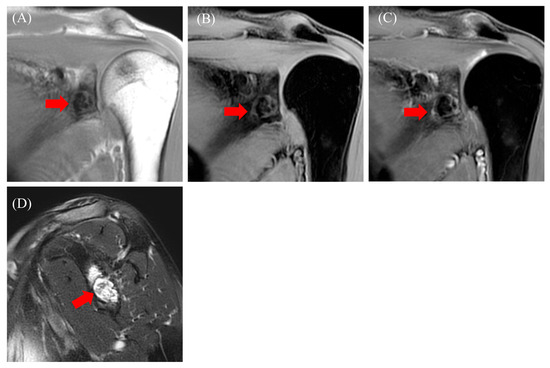

2.1. Case 1

2.2. Case 2